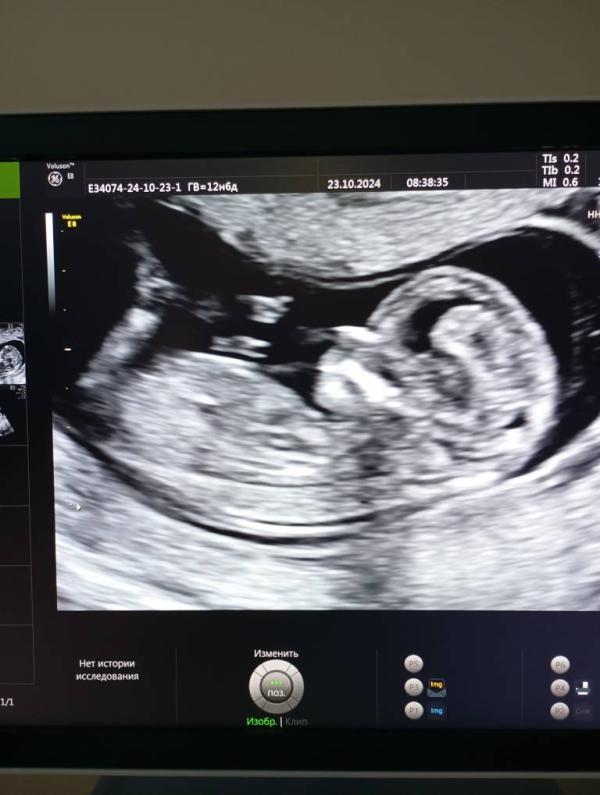

Первый скрининг пройден: малыш машет руками и ногами! Патологий нет, ждем чудо!

А вот и мы сегодня ходили на первый скрининг, врач смеялась сказала язык показывает и руками и ногами машет😘😍все хорошо патологий нет ,ждем тебя наше чудо!